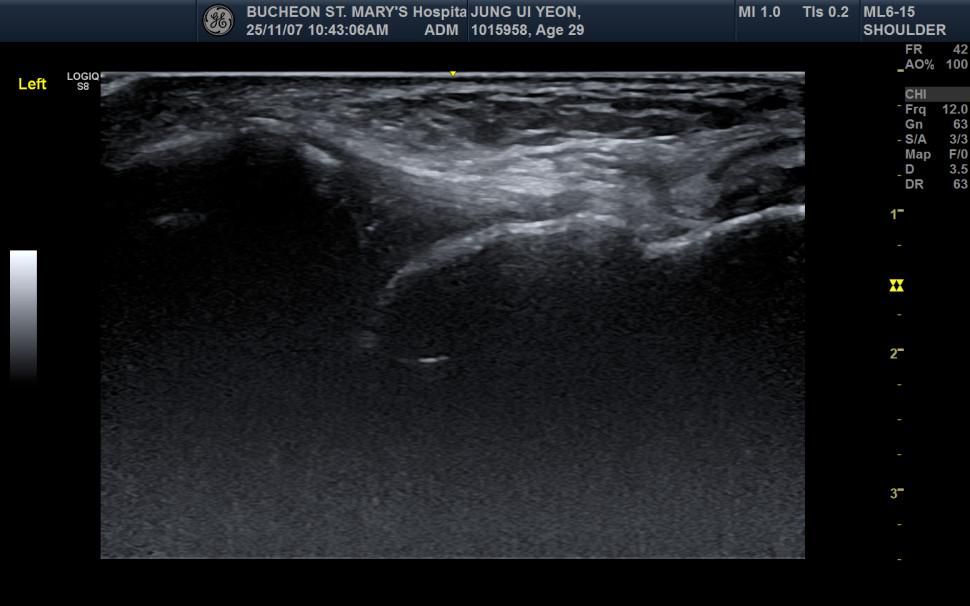

• 2번 째 사진

초음파 이미지를 기준으로 전체적인 구조 설명을 드리겠습니다. 다만 초음파 검사 특성상 프로프 잡은 의사의 주관이 개입되는 면이 있어 설명이 조금 부족하게 느껴지실 수 있습니다.

2. 파열된 인대는 초음파에서 어떻게 보이는가

전거비인대 파열 시 일반적으로 다음 소견 중 일부가 나타납니다.

A. 인대 섬유의 연속성이 끊겨 보임

B.인대가 두꺼워지거나(부종) 내부 에코가 흐려짐

C. 인대 사이에 검은색(무에코) 액체가 보여 혈종·삼출을 의심

D. 심한 완전파열이면 섬유 띠 자체가 보이지 않거나 자리에서 밀려남

사진상 가운데 위치 흰색 음영이 보이는 곳이 전거비 인대가 위치한 곳입니다.

또한 음영이 중간에 끊긴 부위가 있는 것이 파열이 발생한 부위로 예상이 되는데요, 회복이 된다면 음영이 끊긴 부위가 없이 관찰됩니다.